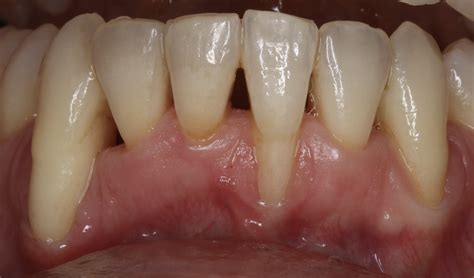

In dentistry, Surgically Facilitated Orthodontic Therapy (SFOT) is an advanced procedure that pinpoints the underlying problems of insufficient alveolar bone and compromised arch forms to optimally. SFOT stands for Surgically Facilitated Orthodontic Therapy. It’s a specialized periodontal procedure that prepares your mouth for orthodontic movement by enhancing the health and thickness of the bone. Surgically facilitated orthodontic therapy (SFOT) is a group of orthodontic procedures; they can be broadly divided into two main categories. [1] The less invasive type uses alveolar corticotomies and. Jan 3, 2026 · Guide to SFoT covers Six Flags Over Texas history, attractions, and tips—your go-to source for park updates, news, and archival features. Surgically facilitated orthodontic therapy is a a surgical procedure performed under the gums to add bone prior to orthodontic treatment, in order to prepare the jaw bones for tooth movement.

Summary: SFOT creates a demineralized bone matrix and augments dentoalveolar deficiencies in the management of dentofacial disharmony malocclusion. Numerous indications and contraindications.